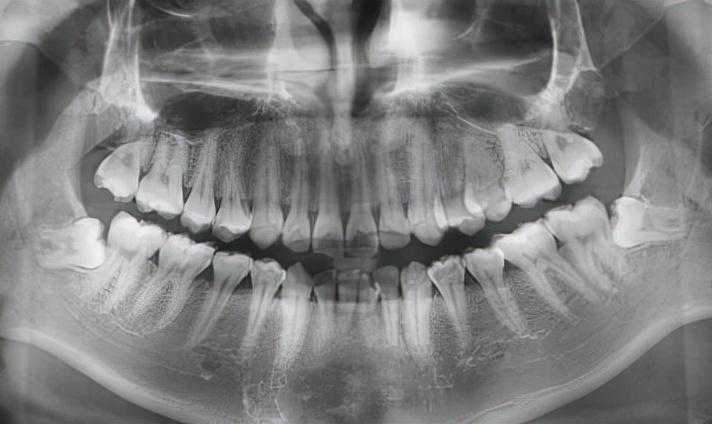

拔牙前拍X光片可以让医生看到肉眼看不到的牙根形态、生长状态。

根据X光片的结果,医生可以更全面地评估拔牙的难度,定制拔牙的方案,向患者更好地解释一些可能存在的风险。

此外,有时候X光片还能发现肉眼看不见的断在牙槽骨里的残根,在手术时可以对拔除残根更加地有把握。

(术前进行拍片,确定牙齿情况)